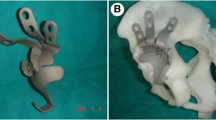

Once the center of the acetabulum was determined, the cage was designed according to the type of acetabular bone defect. The cages were made of grit-blasted titanium to facilitate ongrowth of the bone. In cases in which the supraacetabular bone defect was severe, the site and size of the crests or augment on the superior surface of the cage were tailored to the morphologic features of the individual bone defect. The crests were designed to ensure close contact with the remainder of the superior part of the ilium, thus ensuring vertical support and increasing rotational stability; the space between the crests allowed room for morselized bone allograft. The 3-D printed augments were made from titanium alloy using direct metal laser sintering. The top of each augment, which would be in contact with host bone, contained pores approximately 400 to 500 μm in diameter to permit bone ingrowth, whereas the base was solid so it could be screwed to the cage (Fig. 2).

(A) An AP radiograph shows prosthetic cup loosening with severe acetabular osteolysis 14 years postoperatively in a 70-year-old woman. (B) A CT-based three-dimensional (3-D) reconstruction of the patient’s acetabulum is shown. (C) An individualized custom cage with an artificial iliac wing, 3-D printed support augment, and obturator hook was constructed, and installation was simulated using the rapid-prototyping model. (D) A postoperative AP radiograph shows excellent restoration of the rotational center of the hip.